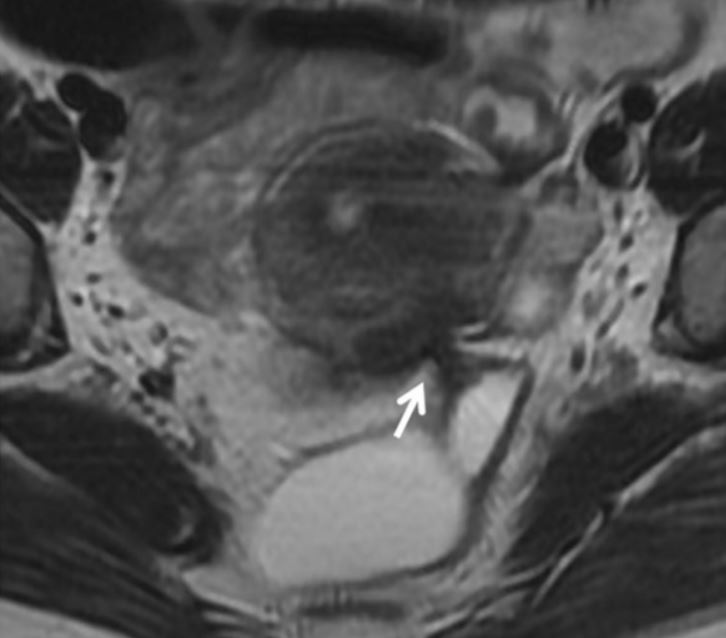

A ressonância magnética consegue detectar apenas os focos de endometriose profunda, já que as lesões superficiais apresentam menos de 1 mm de invasão do peritônio e, portanto, não são identificadas pelos exames de imagem.

Os locais mais frequentemente acometidos pela endometriose profunda são em ordem decrescente: região retrocervical (atrás do colo uterino), incluindo o ligamento uterossacro, intestino, vagina e bexiga.

Endometriose profunda entre o útero e o reto, assinalada na seta branca. Imagem de ressonância magnética para endometriose. Mais imagens e informações podem ser obtidas neste artigo científico. https://www.ncbi.nlm.nih.gov/pubmed/29450853